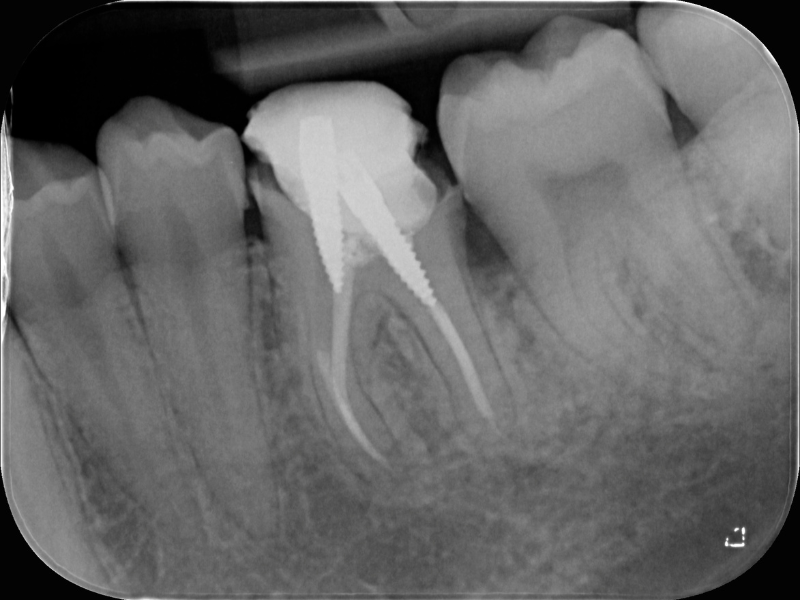

• Rimozione dei materiali da otturazione canalare: confronto tra diverse tecniche

• Recupero della lunghezza di lavoro: la chiave del successo

• Danni iatrogeni: riparazione di perforazioni, superamento di gradini e blocchi

• Gestione delle anatomie apicali alterate e ottenimento di un sigillo efficace